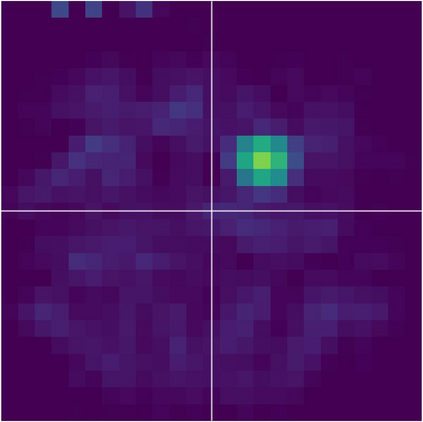

Various imaging modalities allow for time-dependent image reconstructions from measurements where its acquisition also has a time-dependent nature. Magnetic particle imaging (MPI) falls into this class of imaging modalities and it thus also provides a dynamic inverse problem. Without proper consideration of the dynamic behavior, motion artifacts in the reconstruction become an issue. More sophisticated methods need to be developed and applied to the reconstruction of the time-dependent sequences of images. In this context, we investigate the incorporation of motion priors in terms of certain flow-parameter-dependent PDEs in the reconstruction process of time-dependent 3D images in magnetic particle imaging. The present work comprises the method development for a general 3D+time setting for time-dependent linear forward operators, analytical investigation of necessary properties in the MPI forward operator, modeling aspects in dynamic MPI, and extensive numerical experiments on 3D+time imaging including simulated data as well as measurements from a rotation phantom and in-vivo data from a mouse.